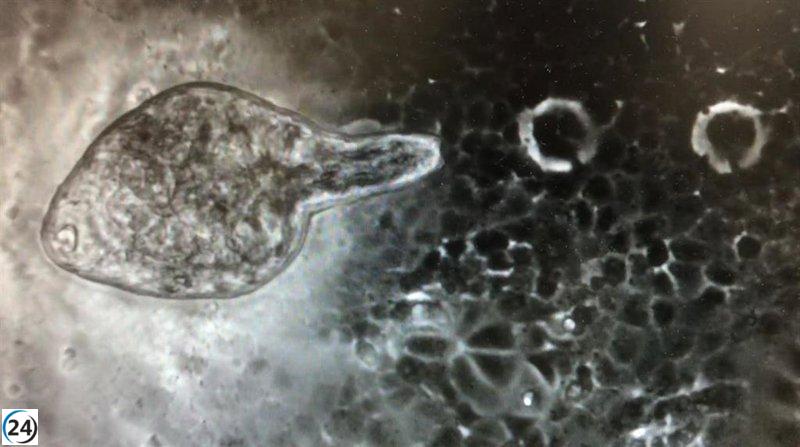

En esta investigación se ha utilizado la especie de helminto Fasciola hepatica, que tiene un ciclo de vida complejo y puede infectar a los humanos a través de la ingestión de metacercarias en agua o plantas acuáticas. Una vez dentro del cuerpo humano, las larvas de este helminto liberan una proteína llamada FhNEJ, que induce cambios en las proteínas de las células huésped y estimula una respuesta inmune positiva.